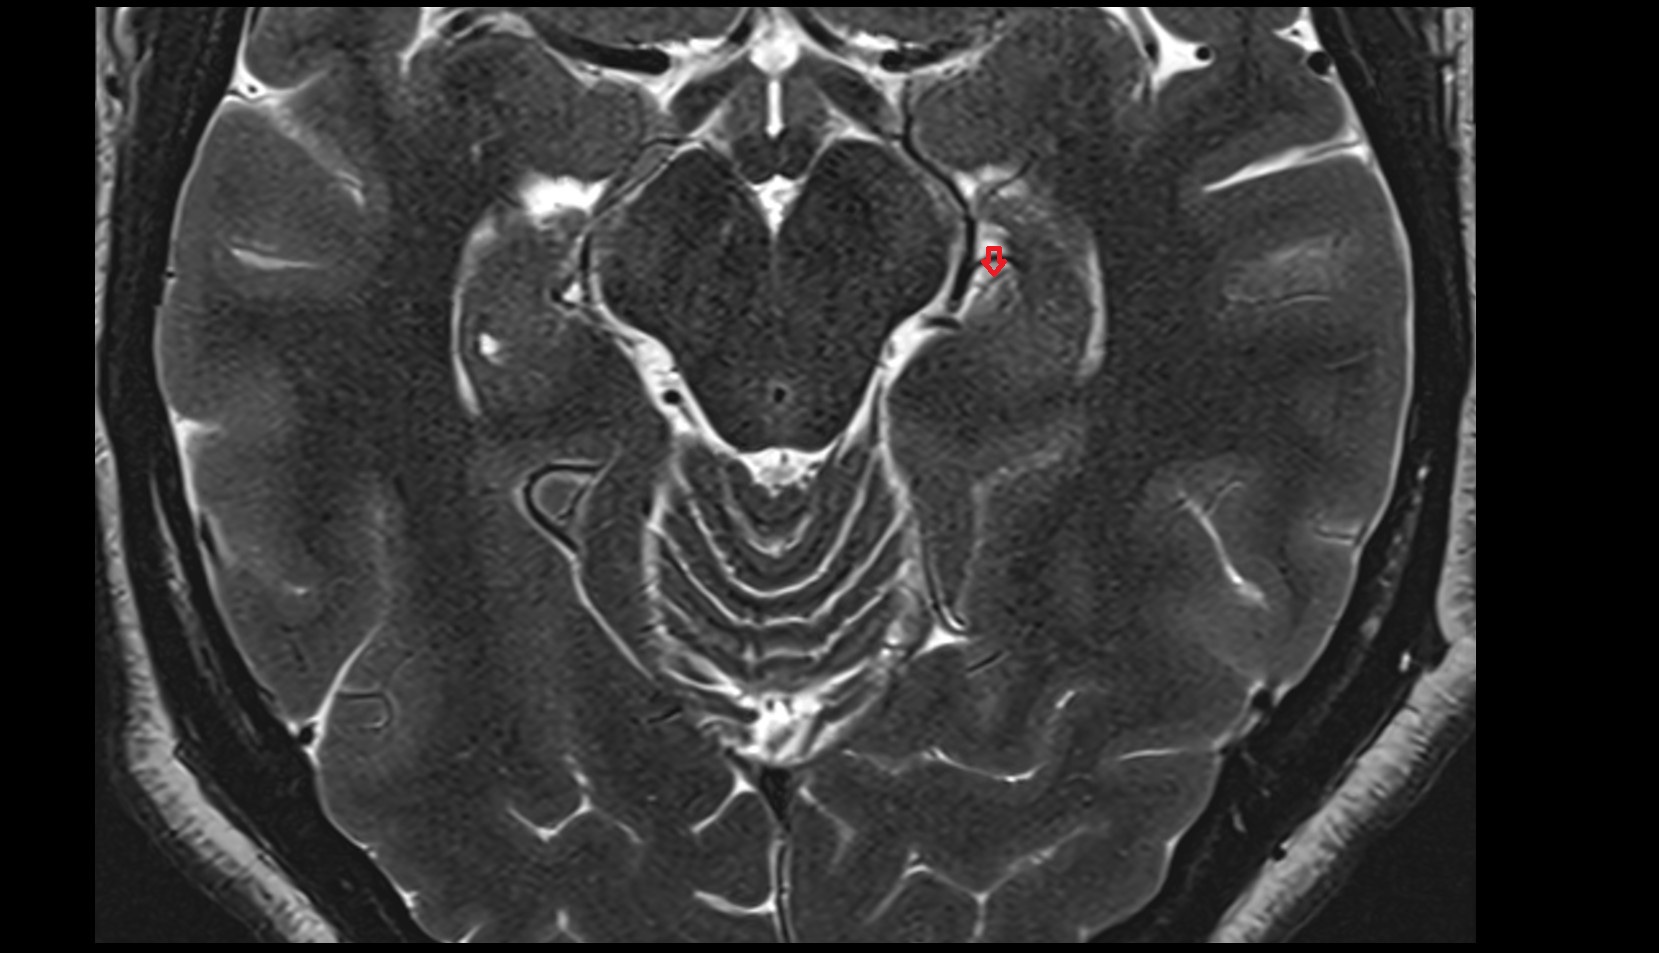

- Cerebellum

- Flocculus

- Cerebellar tonsil (H IX)

- Central lobule (II & III) of Cerebellum

- Culmen (IV, V) of Cerebellum

- Declive (VI) of Cerebellum

- Nodule of vermis (X)